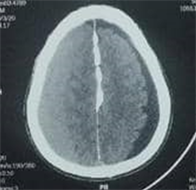

A 65-year-old man presented to the hospital with a 2-month history of recurrent headache requiring oral medication without noticeable improvement, and dizziness. There was an history of head injury from a traffic accident 3 months ago. His vitals parameters were within normal limits with no neurological deficits. The result of the Brain CT scan showed right frontal-parietal CSDH with mass effect associated to left frontal-parietal hygroma (Figure 1). After hospitalization and normal preoperative assessment, CSDH was evacuated through 2 burr holes and hygroma through 1 burr hole. Postoperatively the patient presented with agitation and headaches. CT scan is performed and showed an acute hematoma mimicking an extradural hematoma and frontal pneumocephalus (Figure 2). A

Figure 2. Post operative CT scan: acute hematoma mimicking an extradural hematoma and frontal pneumocephalus.